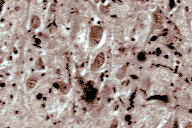

Dystrophic neurites Diffuse Lewy body disease, hippocampus.

Immunohistochemical stain for ubiquitin, showing coarse dystrophic neurites in the CA2 sector.